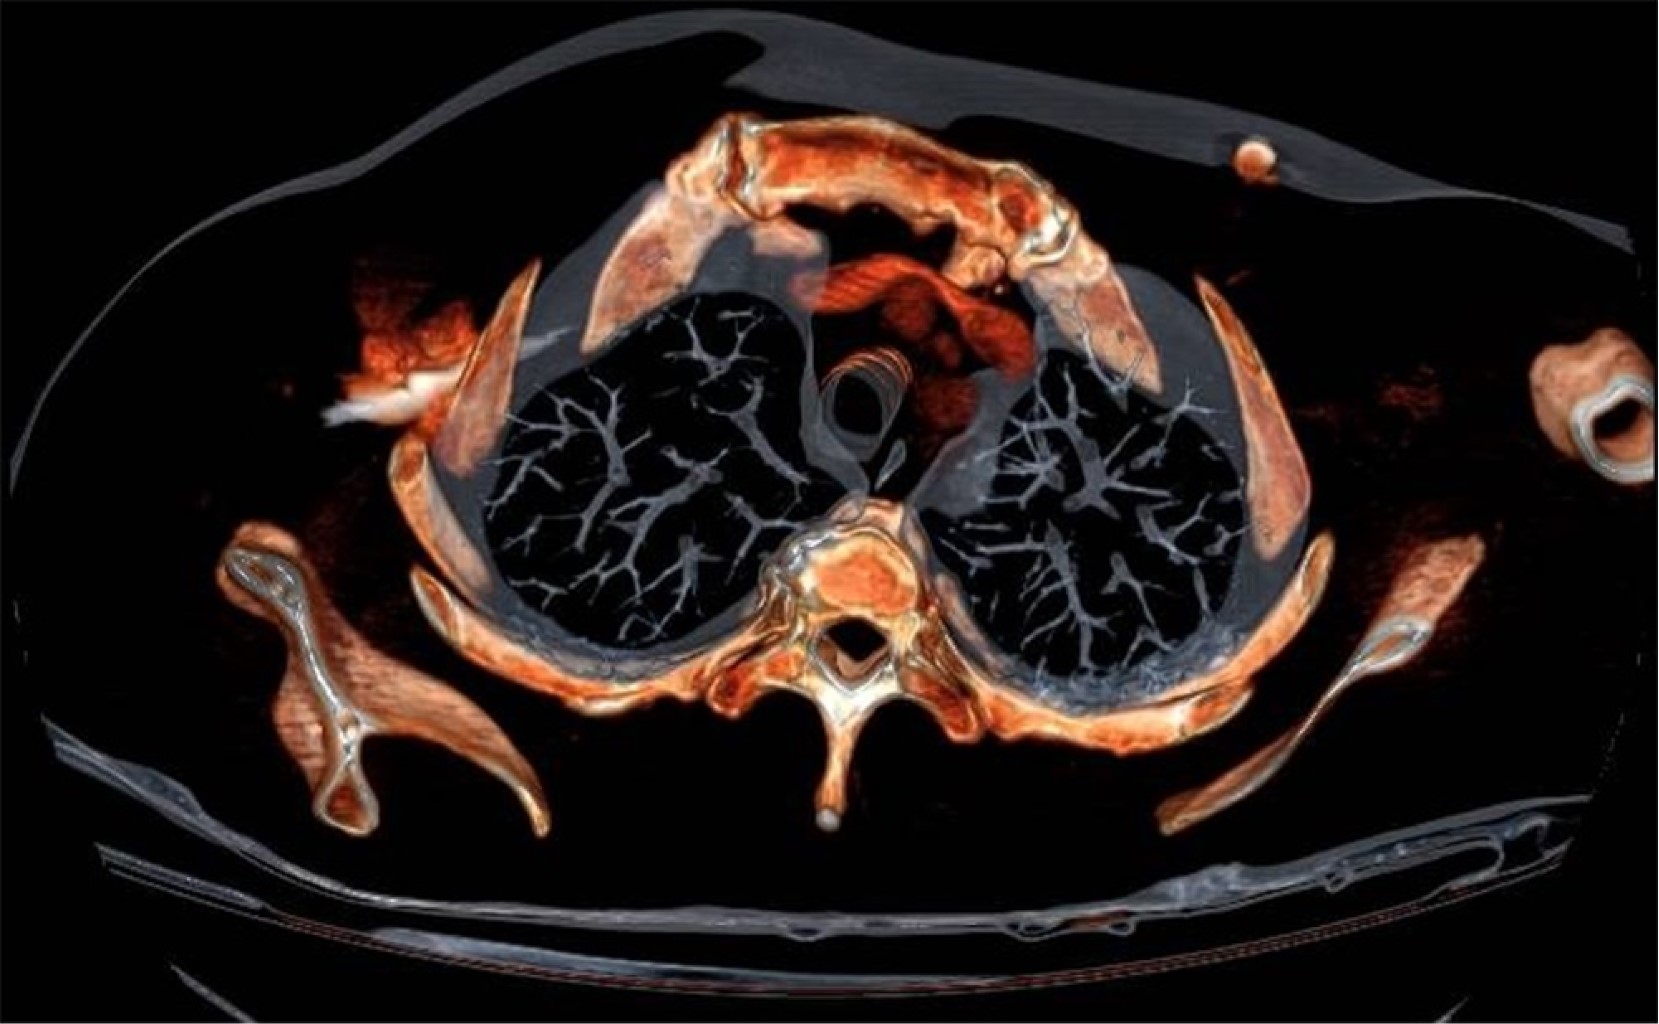

Malposition of central venous catheters is associated with important and underestimated risks. Although some factors have been related with malposition, its cause is generally not diagnosed, and it seems to have multifactorial origin. We present two cases of central venous catheter malposition due to unusual anatomical causes, diagnosed in the perioperative period. In the first case, superior vena cava agenesis was diagnosed during mitral replacement by sternotomy, which was logically associated with malposition of the inserted central line. The use of catheters and devices through jugular and subclavian veins in patients with this infrequent pathology is associated with important limitations and serious potential complications. In the second case, an undiagnosed goiter causes bilateral and simultaneous malpositioning of two inserted central venous catheters, in the context of an emergency situation, in both internal jugular veins.

Figure 2